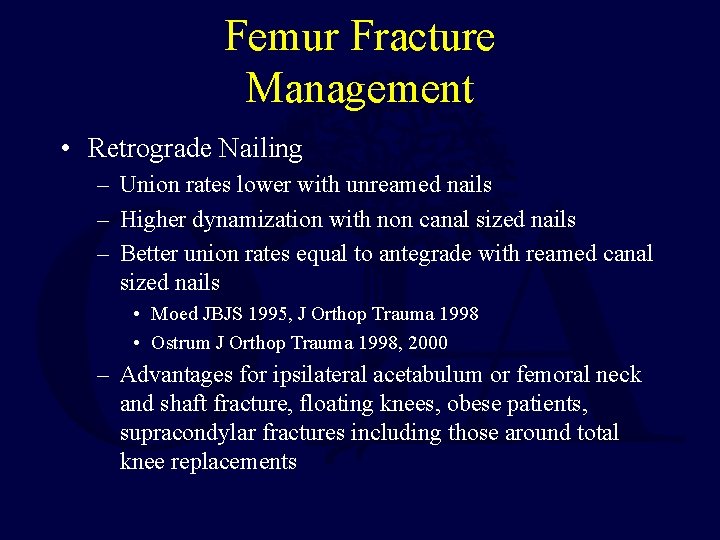

Femur Fracture Management • Retrograde Nailing – Union rates lower with unreamed nails – Higher dynamization with non canal sized nails – Better union rates equal to antegrade with reamed canal sized nails • Moed JBJS 1995, J Orthop Trauma 1998 • Ostrum J Orthop Trauma 1998, 2000 – Advantages for ipsilateral acetabulum or femoral neck and shaft fracture, floating knees, obese patients, supracondylar fractures including those around total knee replacements